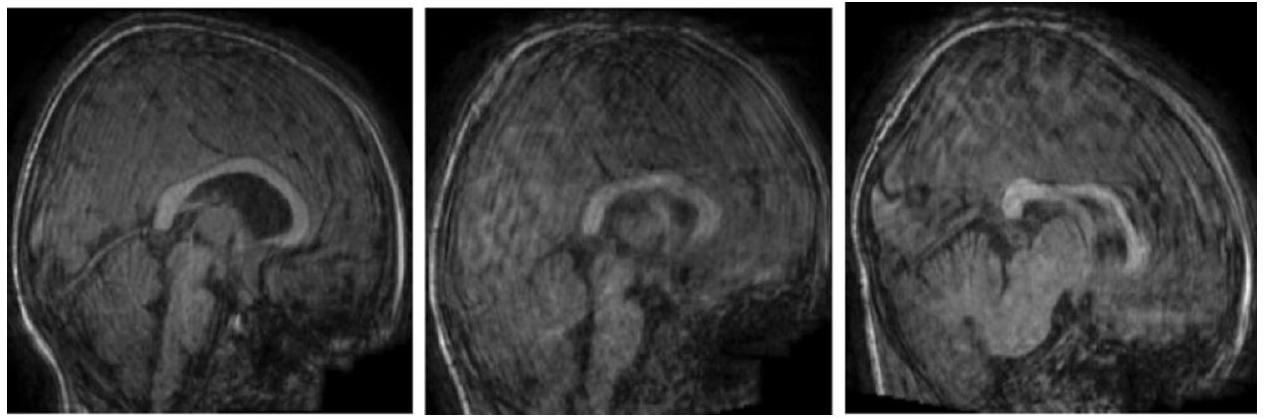

The fact that the rapid and definitive diagnosis of autism cannot be made today and that autism cannot be treated provides an impetus to look into novel technological solutions. To contribute to the resolution of this problem through multiple classifications by considering age and gender factors, in this study, two quadruple and one octal classifications were performed using a deep learning (DL) approach. Gender in one of the four classifications and age groups in the other were considered. In the octal classification, classes were created considering gender and age groups. In addition to the diagnosis of ASD (Autism Spectrum Disorders), another goal of this study is to find out the contribution of gender and age factors to the diagnosis of ASD by making multiple classifications based on age and gender for the first time. Brain structural MRI (sMRI) scans of participators with ASD and TD (Typical Development) were pre-processed in the system originally designed for this purpose. Using the Canny Edge Detection (CED) algorithm, the sMRI image data was cropped in the data pre-processing stage, and the data set was enlarged five times with the data augmentation (DA) techniques. The most optimal convolutional neural network (CNN) models were developed using the grid search optimization (GSO) algorism. The proposed DL prediction system was tested with the five-fold cross-validation technique. Three CNN models were designed to be used in the system. The first of these models is the quadruple classification model created by taking gender into account (model 1), the second is the quadruple classification model created by taking into account age (model 2), and the third is the eightfold classification model created by taking into account both gender and age (model 3). ). The accuracy rates obtained for all three designed models are

Data pre-processing